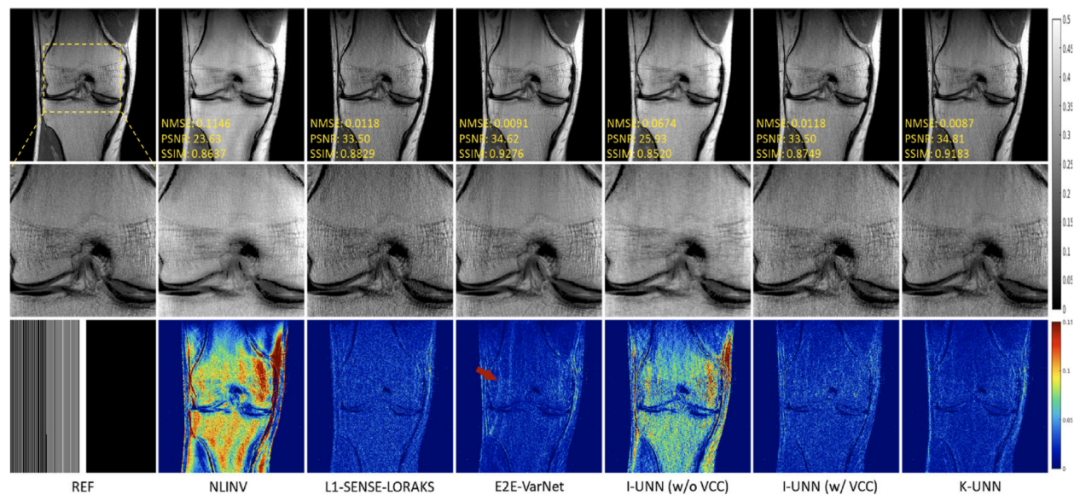

磁共振利用多通道线圈接收人体生理信号,多线圈的数据间具有很强的相关性。团队针对磁共振成像中全采数据难以获得的巨大挑战,提出利用线圈间数据相关性这一物理先验,来构建磁共振物理驱动的无监督深度神经网络成像模型,并分析了网络的误差上界,为成像可靠性提供保障。实验结果(图1)表明,该方法无需训练数据就能够重建出高质量图像,且效果与需要训练数据方法类似。研究成果发表在医学成像领域著名期刊Medical Image Analysis。

图1. 5倍加速重建结果